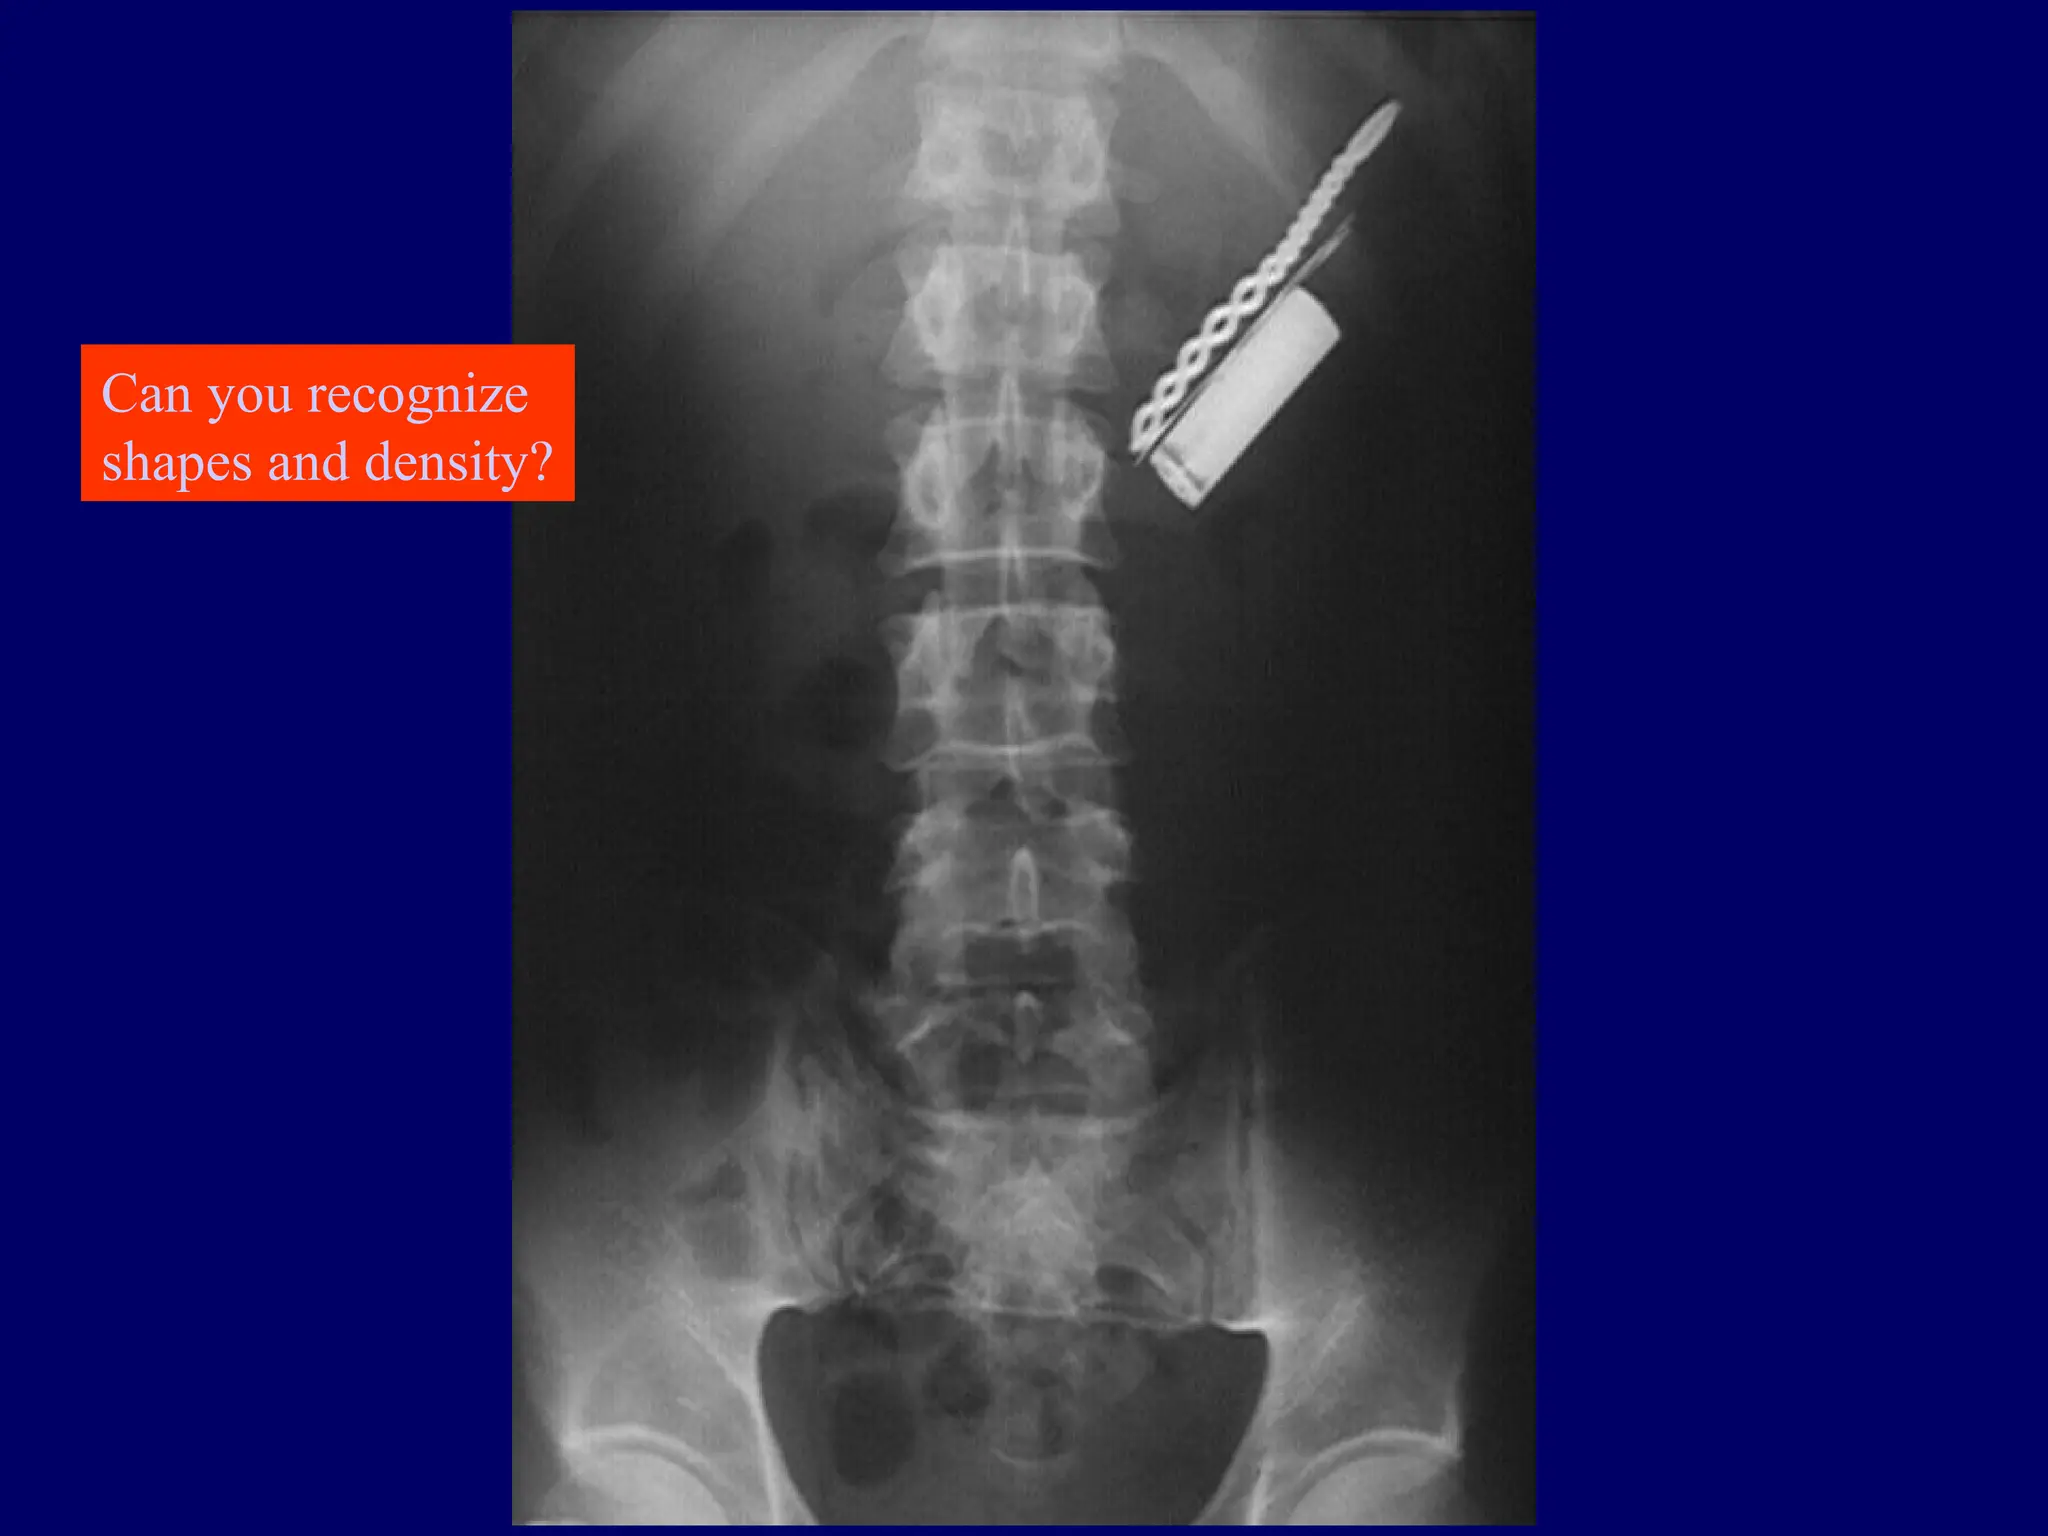

Can you recognize

shapes and density?

A broken centralvenous catheter has migrated into the right lower lobe pulmonary artery